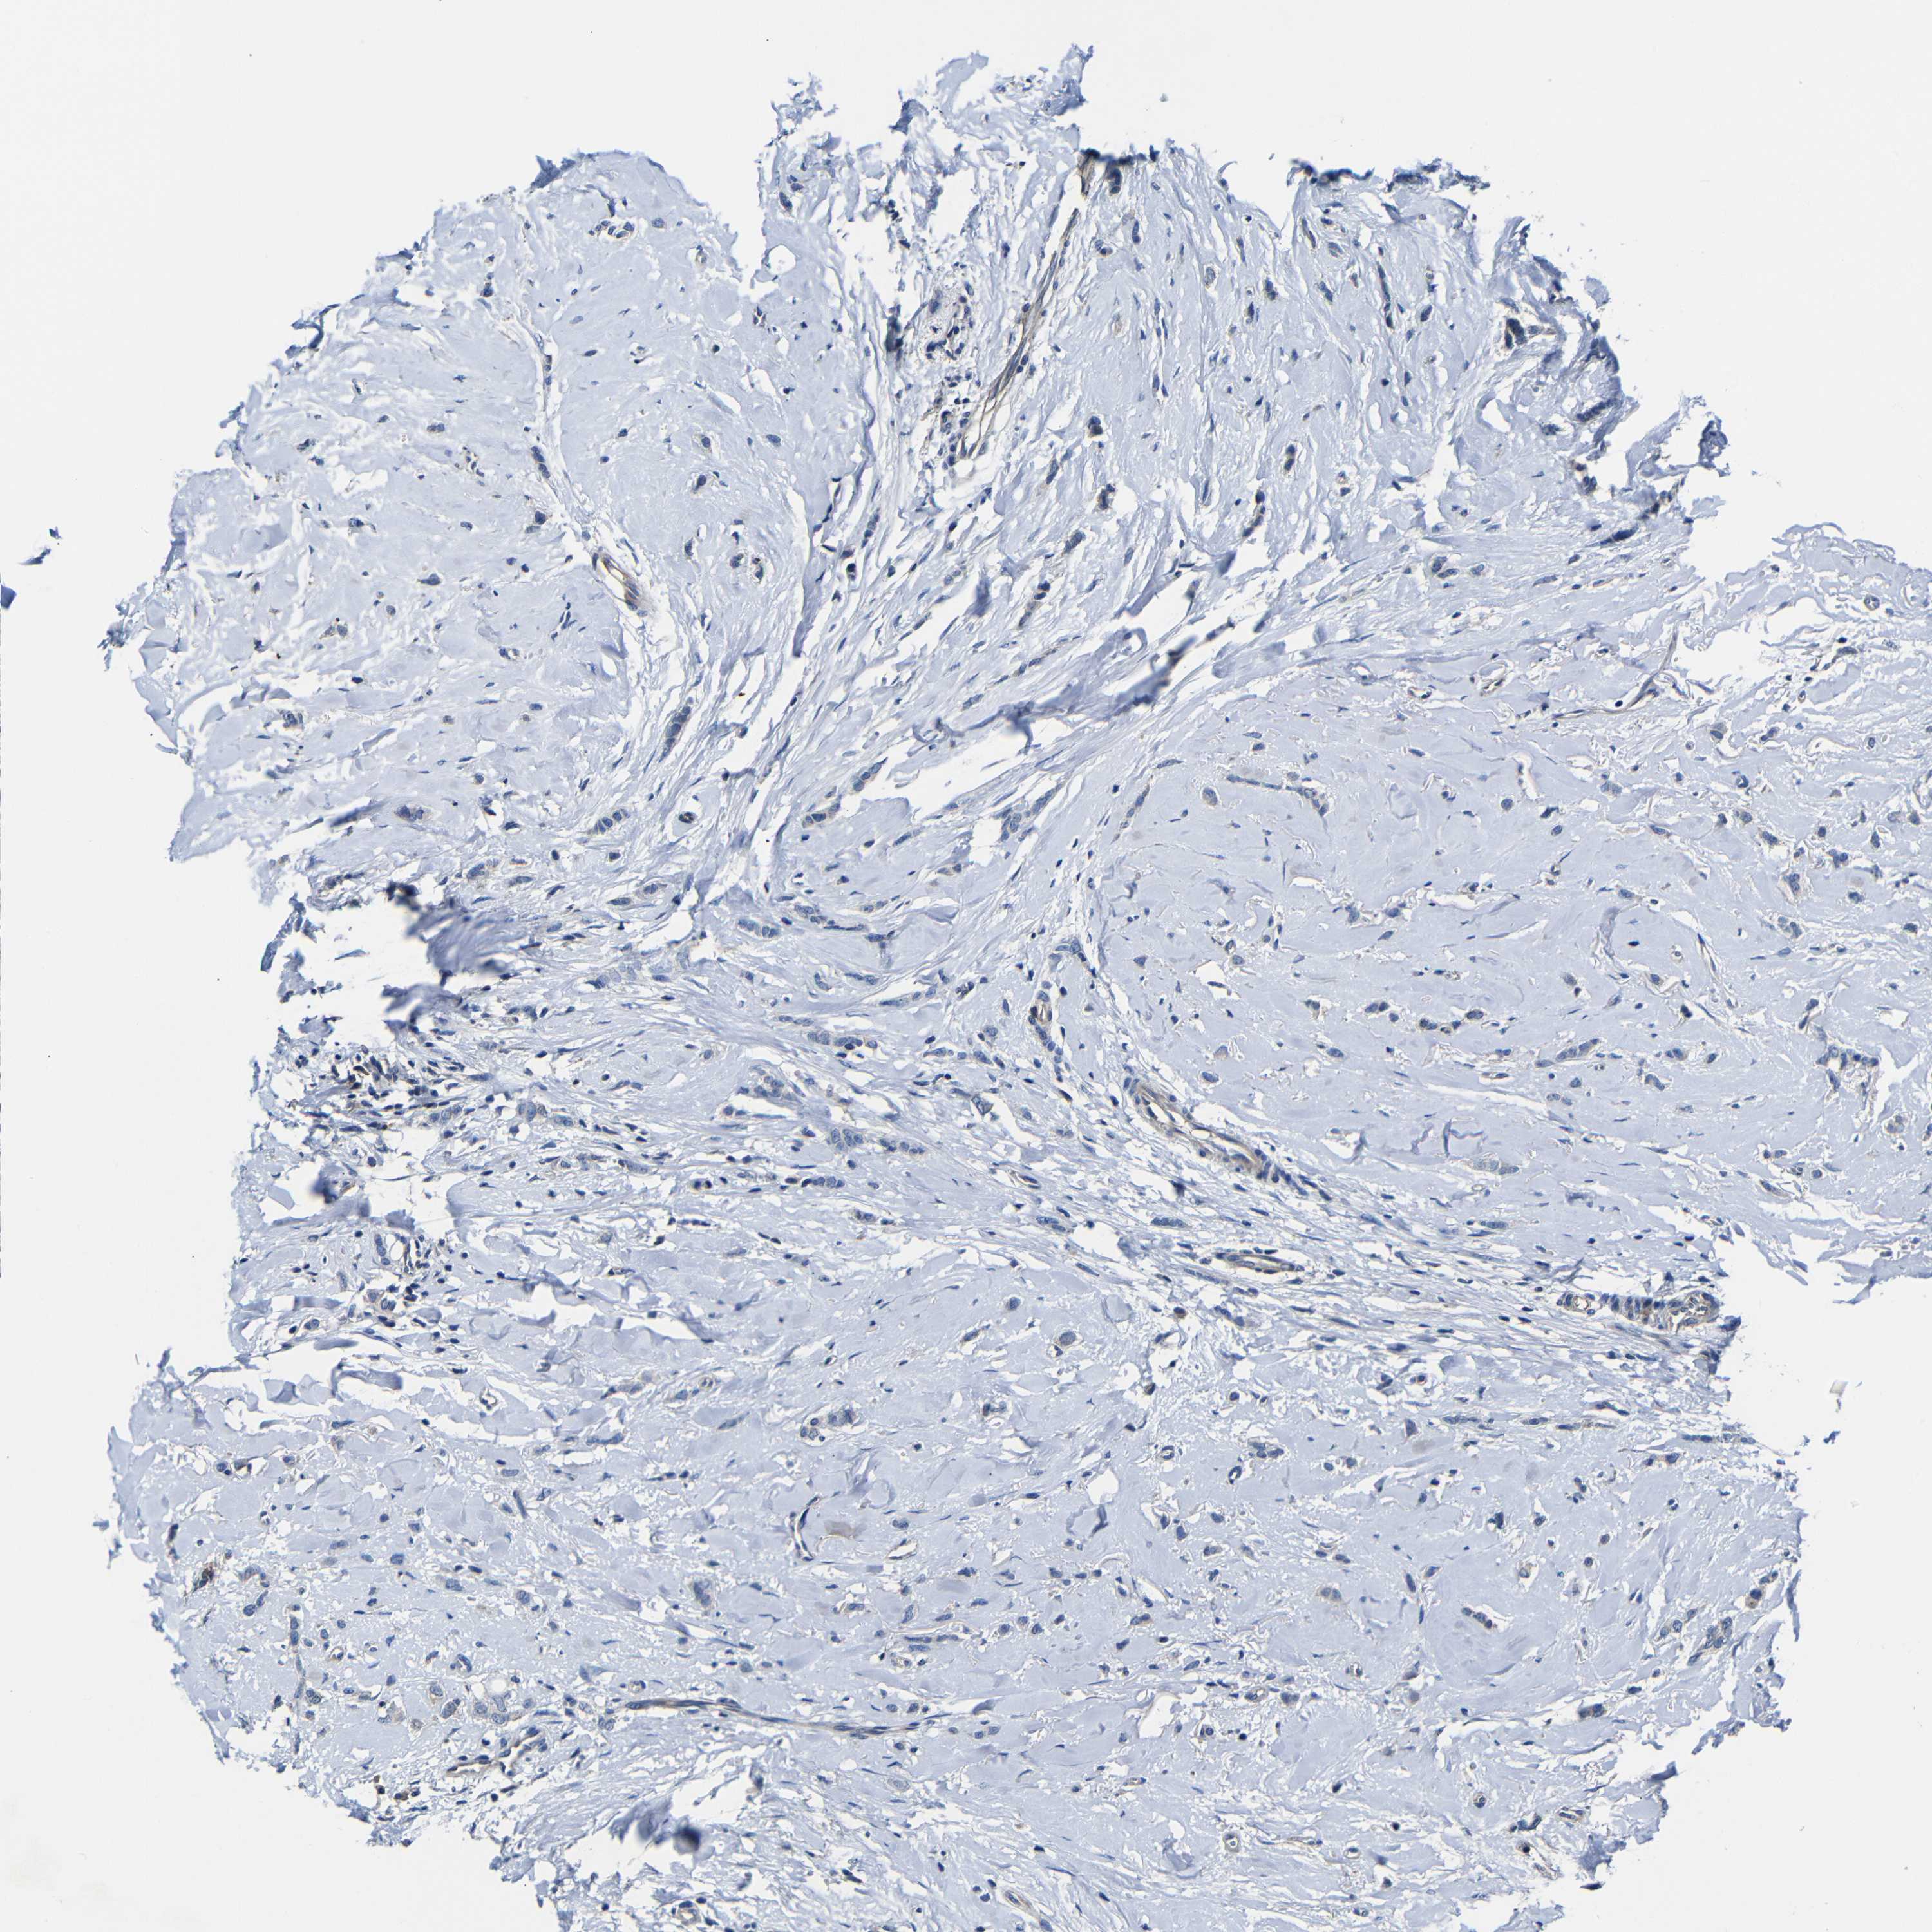

BRCA TCGA BRCA VALIDATION PROTEIN EXPRESSION

ANTIBODIES

AND

VALIDATION